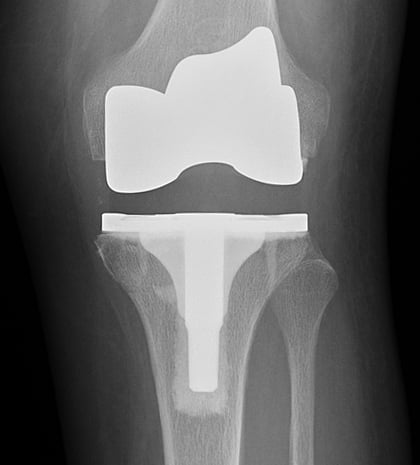

The selection of knee replacement prosthesis design and materials depends on each individual patient. The main implant components are made of metal – usually titanium or chrome-cobalt alloys. The implants are fixated in place either with a cement bonding agent or by osseointegration, in which the patient’s bone grows into a porous metal surface. A plastic platform or spacer will be inserted between the tibial and femoral implant surfaces. The spacer is made of polyethylene.

Most femoral components are made of metal alloys (cobalt chromium) or metal-ceramic alloys (oxidized zirconium). The patellar component is plastic (polyethylene). The tibial insert component is also plastic (polyethylene). The tibial tray component can be made of the following materials:

Anteroposterior (front-to-back) X-ray of total knee replacement implants.